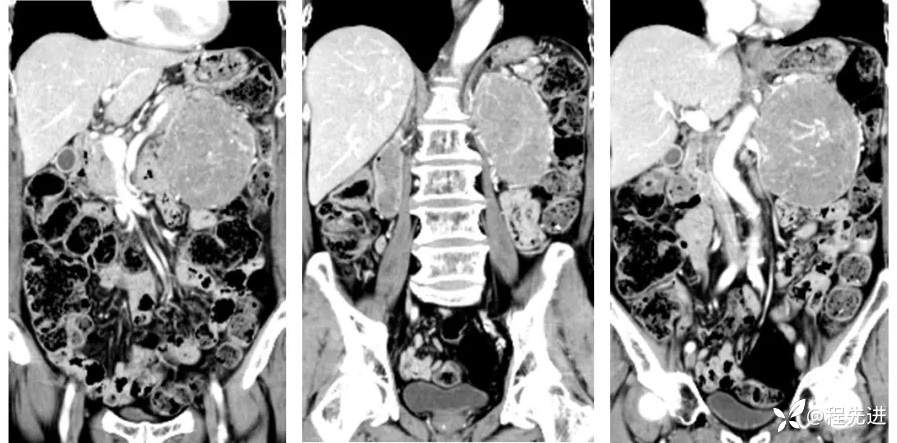

冠状位重建: